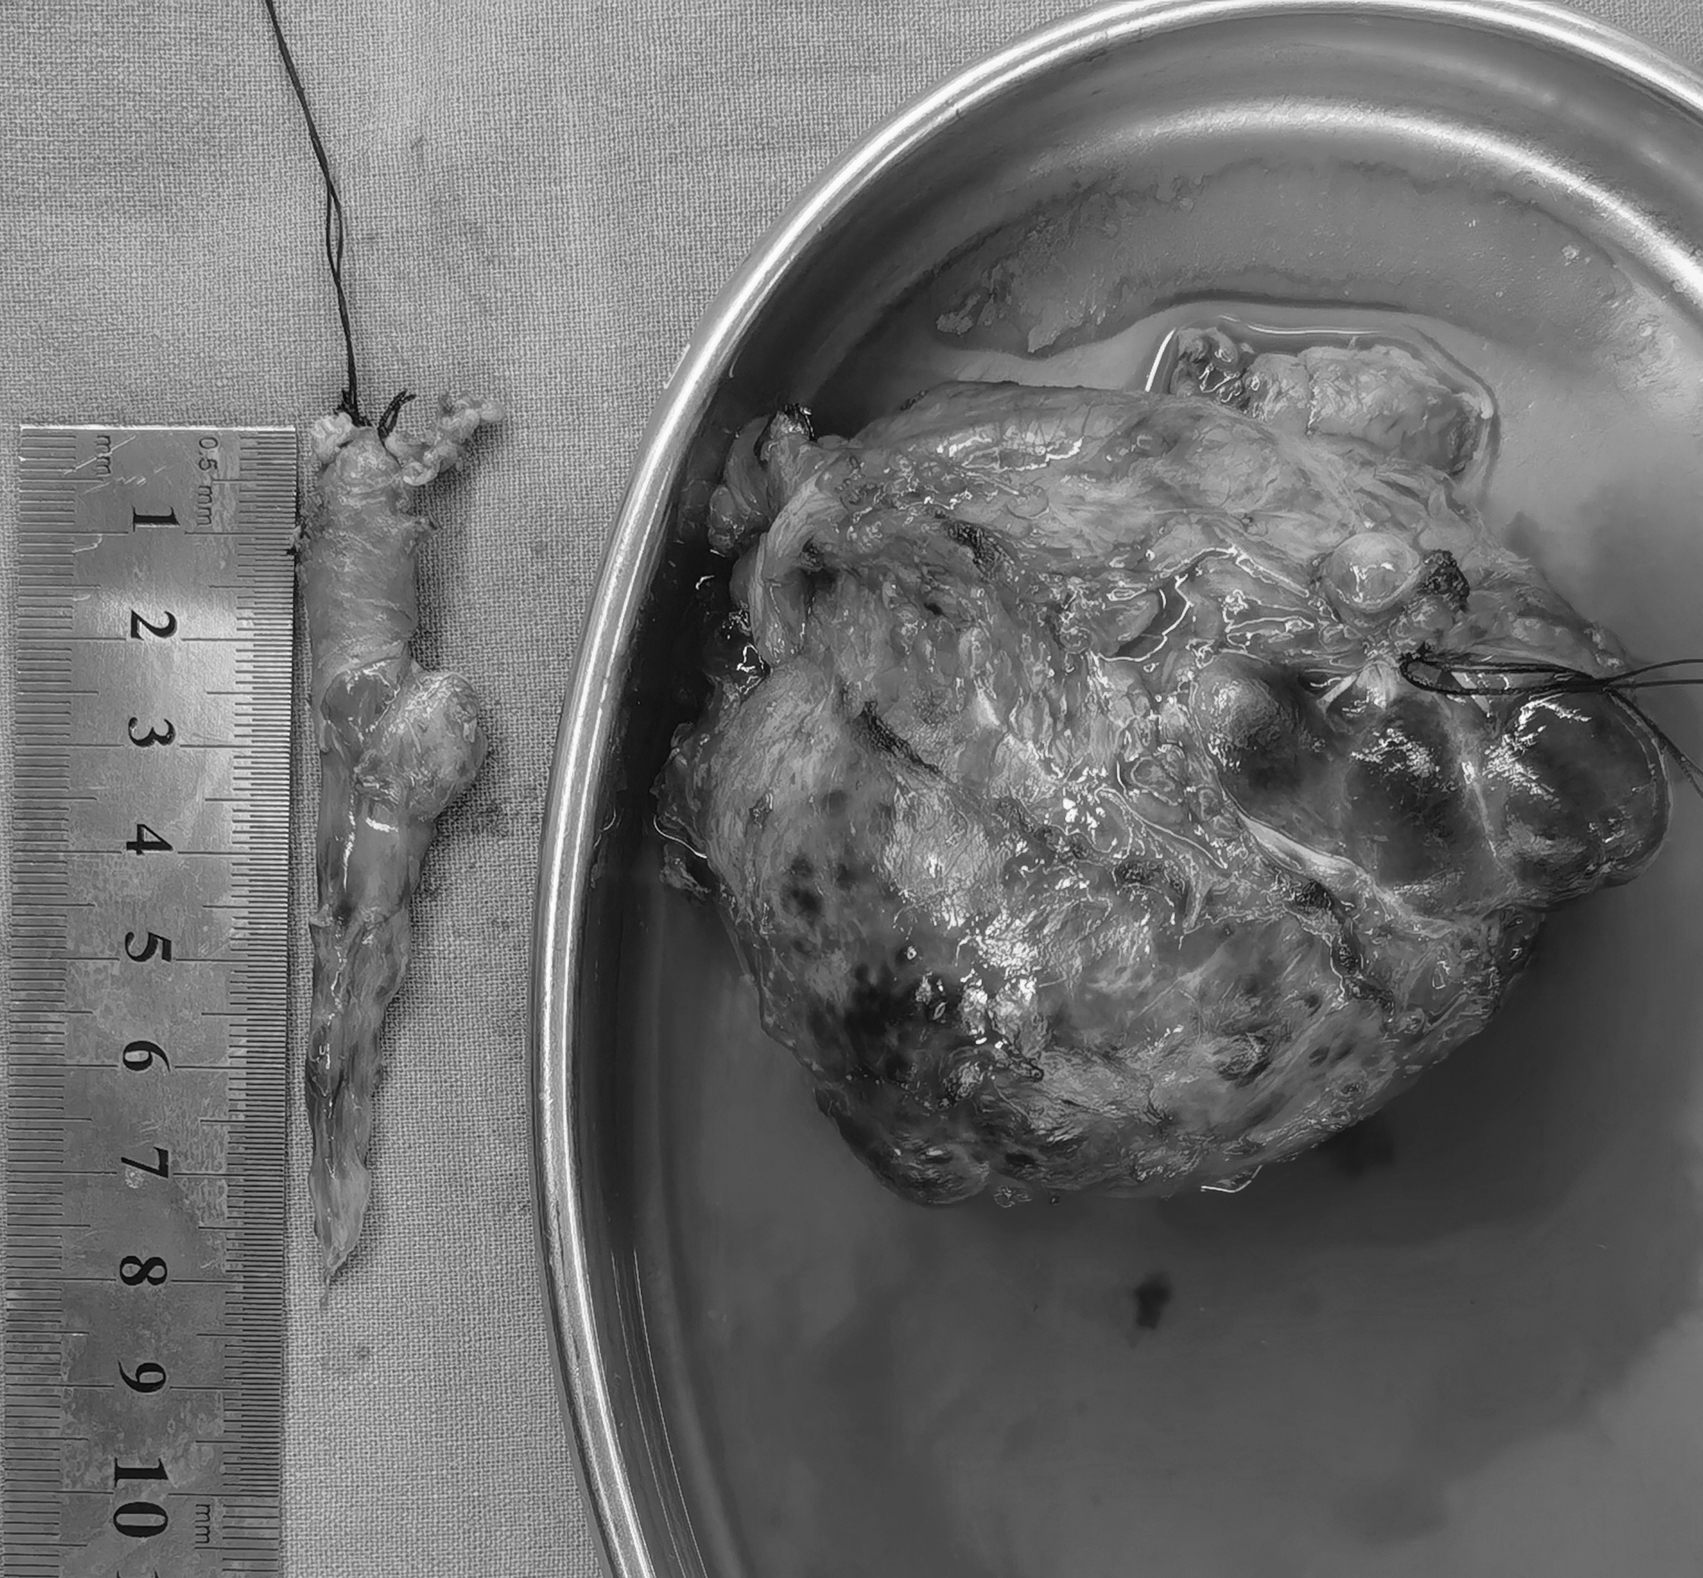

【“爱笑的女孩”婷婷不幸离世,年仅11岁,生前遗憾或是未能见妈妈一面】11月2日凌晨5时许,来自河南濮阳的抗癌博主“婷婷打怪兽”不幸离世,年仅11岁。3日,该账号的运营者赵女士告诉@极目新闻 记者,账号记录的是侄女婷婷的抗癌生活,希望她能被更多人记住,也希望肾母细胞瘤这个疾病被更多人知晓。#家人提前三个月为11岁抗癌女孩庆生#婷婷的病情始于2023年6月底,正在读三年级的她在学校出现腹痛症状。起初家人以为是普通肠胃不适,在村里诊所拿药后未见好转,随后辗转多个医院被确诊为肾母细胞瘤。“我们之前从没听过这个病,一点了解都没有,当时整个人都蒙了。”赵女士回忆道。确诊后仅四五天,婷婷接受了第一次手术,右肾被切除。术后家人本以为病情能得到控制,却没想到这只是抗争的开始。2023年11月,距离第一次手术仅半年,婷婷的病情复发,肿瘤转移至肝门及右肾手术末端,家人只能带她进行第二次手术,切除转移病灶。两次手术后,化疗、放疗成为婷婷生活的常态。2024年初,病情暂时稳定的婷婷曾重返校园两个月,彼时她已升至四年级。“她成绩特别好,之前在班里一直是前三名,半年没上学,晚上学到十一点也要把落下的课程补回来,考试还能考九十多分。”赵女士说。2025年3月,家人带婷婷到济南做全身检查,结果显示无复发迹象,婷婷重拾信心。“我们当时都以为她要好了。”赵女士说。然而,今年4月,婷婷在郑州复查时被查出肝门肿瘤复发,化疗后更出现严重骨髓抑制,险些丧命。8月底再次检查显示肿瘤扩散,医生表示已无治疗价值。“最后这段时间她就躺在家里,完全不想出门,肚子里长满了肿瘤,离开的时候肚子跟六个月的孕妇一样大。